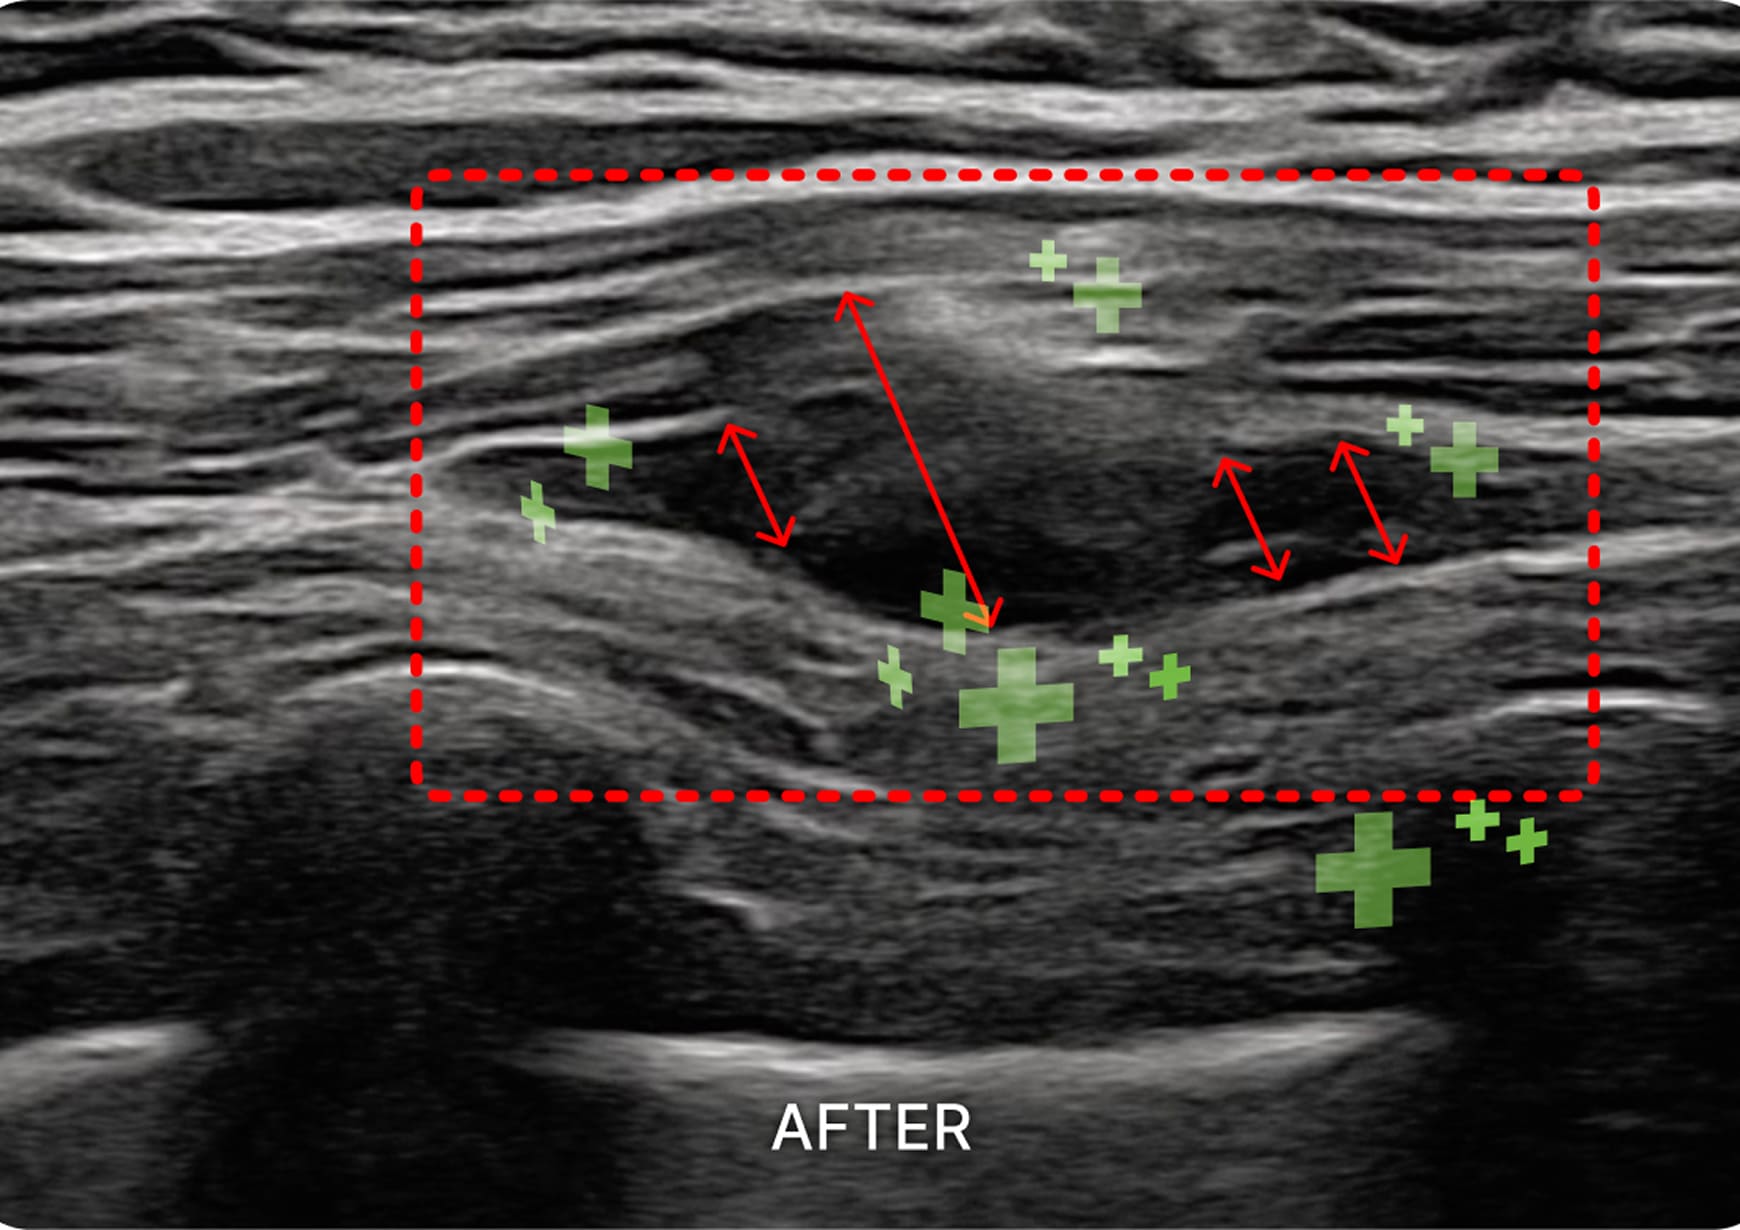

1. 초음파 시술

초음파를 활용하여 근육과 신경 문제를

정확히 진단하고 치료하여 통증과 기능

이상을 개선하는 시술입니다.

요부 교감신경총 / 하복신경총

대장의 소화 흡수 기능을 개선하고, 디스크, 협착증에

기반하지 않은 하지 저림 증상 및 비뇨 생식기계 증상을 개선합니다.

골반신경총

자궁 경부, 방광, 요도의 수축 이완에 관여하는

신경절을 자극하여 빈뇨와 대하 등의 증상을 해결합니다.